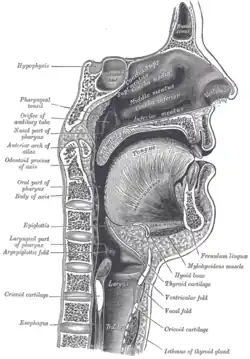

Articulation

In a third process of speech production, articulation, mobile and immobile structures of the face (articulators) adjust the shape of the mouth, pharynx and nasal cavities (vocal tract) as the vocal fold vibration sound passes through producing varying resonant frequencies.